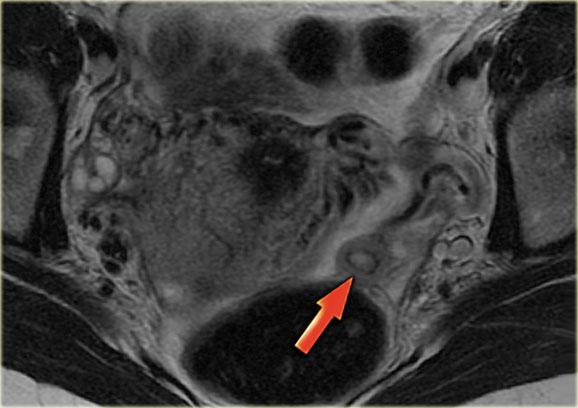

Nang hoàng thể trên MRI: hình ảnh chuỗi xung T2W mặt cắt ngang cho thấy nang hoàng thể đang thoái triển (mũi tên).

Đây là hình ảnh bình thường.

Buồng trứng phải cũng bình thường.